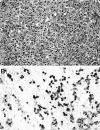

Medullary carcinomas of the pancreas are a recently described, histologically distinct subset of poorly differentiated adenocarcinomas that may have a unique pathogenesis and clinical course. To further evaluate these neoplasms, we studied genetic, pathological, and clinical features of 13 newly identified medullary carcinomas of the pancreas. Nine (69%) of these had wild-type K-ras genes, and one had microsatellite instability (MSI). This MSI medullary carcinoma, along with three previously reported MSI medullary carcinomas, were examined immunohistochemically for Mlh1 and Msh2 expression, and all four expressed Msh2 but did not express Mlh1. In contrast, all of the medullary carcinomas without MSI expressed both Msh2 and Mlh1. Remarkably, the MSI medullary carcinoma of the pancreas in the present series arose in a patient with a synchronous but histologically distinct cecal carcinoma that also had MSI and did not express Mlh1. The synchronous occurrence of two MSI carcinomas suggests an inherited basis for the development of these carcinomas. Indeed, the medullary phenotype, irrespective of MSI, was highly associated with a family history of cancer in first-degree relatives (P < 0.001). Finally, one medullary carcinoma with lymphoepithelioma-like features contained Epstein-Barr virus-encoded RNA-1 by in situ hybridization. Therefore, because of medullary carcinoma's special genetic, immunohistochemical, and clinical features, recognition of the medullary variant of pancreatic adenocarcinoma is important. Only by classifying medullary carcinoma as special subset of adenocarcinoma can we hope to further elucidate its unique pathogenesis.